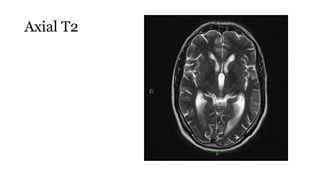

Axial T2

T2

• Standard sequence

• Fluid is bright (hyper-intense)

• White matter is darker than grey